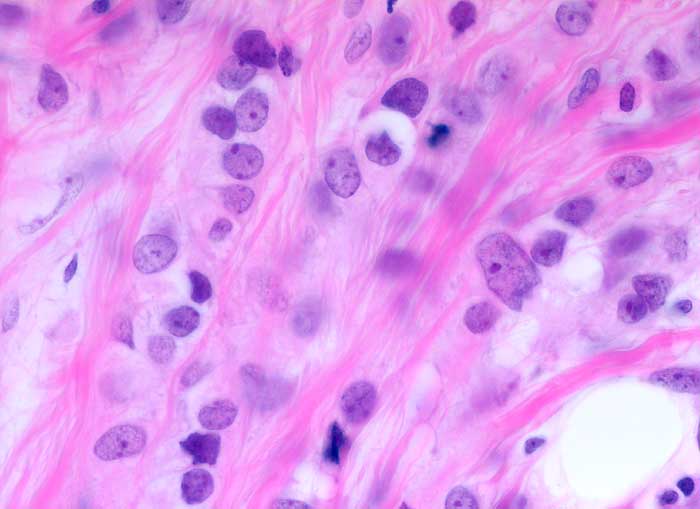

invasiv lobuläres Mammakarzinom

In Einerreihen hintereinander gänsemarschartig angeordnete monomorphe kleine Tumorzellen mit geringen Atypien.

Histologie

630